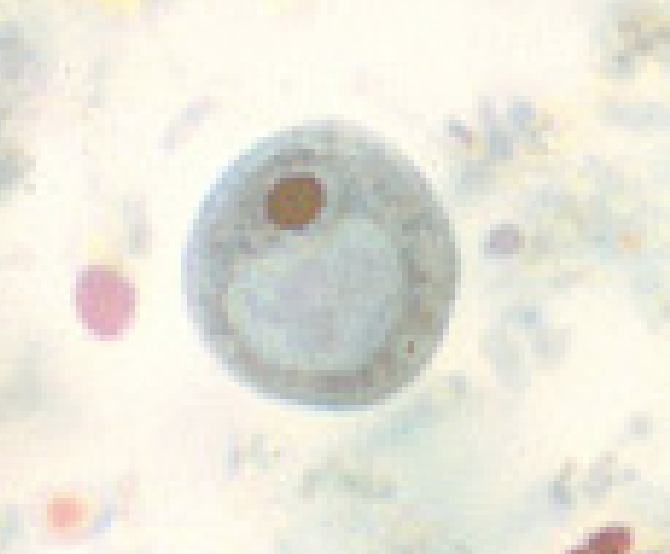

Iodamoeba butschlii

What parasite has a glycogen vacuole

Iodamoeba butschlii

What color does the glycogen vacuole stain with iodine

brown

Iodamoeba butschlii cyst

Iodamoeba butschlii cyst